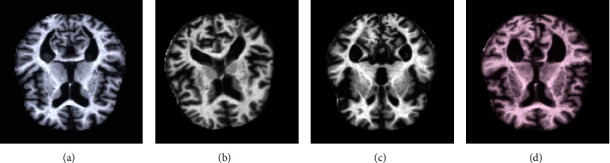

Abstract Image